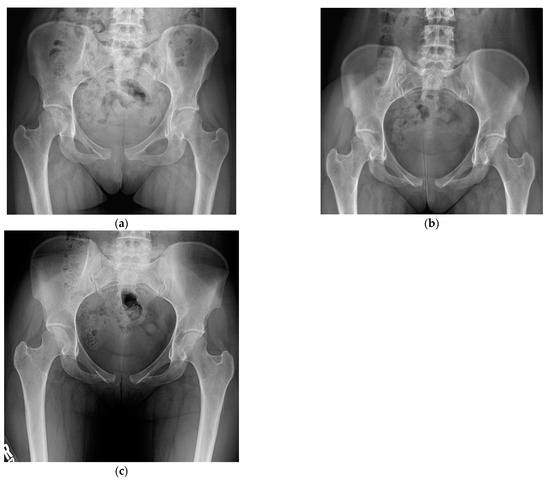

With the binder in place, repeat imaging demonstrated the pubic symphysis diastasis was reduced to 1.2 cm (Figure 2). An orthopaedic consult was placed, and the assessment was made that the symphyseal ligaments and right-sided anterior sacroiliac ligaments were torn.

Figure 2. AP pelvis radiograph following binder application demonstrating the pubic symphysis diastasis reduced to 1.2 cm.